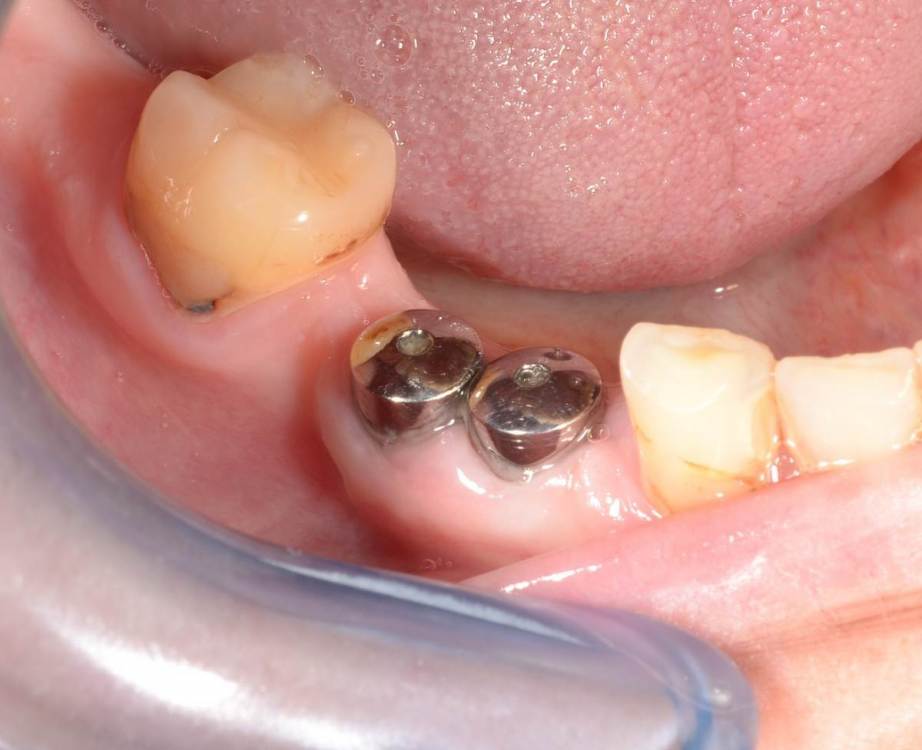

Большой Зеленый Опубликовано 27 мая, 2022 Поделиться Опубликовано 27 мая, 2022 Через 9 лет. Есть немного рецессии.. 2 Ссылка на комментарий

pit Опубликовано 27 мая, 2022 Поделиться Опубликовано 27 мая, 2022 4 часа назад, Большой Зеленый сказал: Через 9 лет. Есть немного рецессии.. Это связано исключительно с вестибулярной позицией импланта. Это как раз к вопросу про те минимальные 2мм до вестиболярной стенки, вне зависимости есть она или ты ее создаешь. Ссылка на комментарий

Большой Зеленый Опубликовано 27 мая, 2022 Поделиться Опубликовано 27 мая, 2022 4 часа назад, pit сказал: Это связано исключительно с вестибулярной позицией импланта. Это как раз к вопросу про те минимальные 2мм до вестиболярной стенки, вне зависимости есть она или ты ее создаешь. С тех пор я стал хитрее умнее и опытнее ))) 1 час назад, alboard сказал: А в чем смысл ее сохранности, если препарируя под имплантат вы все равно ее в большинстве случаев сносите? Первичная стабильность импланта зачастую достигается только перегородкой.. Ссылка на комментарий

Большой Зеленый Опубликовано 28 мая, 2022 Поделиться Опубликовано 28 мая, 2022 12 часов назад, Женька сказал: @Большой Зеленый это вроде ваш старый кейс? напомните пожалуйста, тут присыпка+мембранинг вестибулярно и вестибулярным лоскутом слегка послабленным всё закрыли? Да все так и есть как Вы и описали. Работе почти 10 лет. Присыпка мп3 от остеобила сверху "ильгамовская" губка . Считаю что результат вполне удовлетворительный. Рецессия обусловлена как уже сказали выше вестибулярным положением импланта ,ну и недозаглублен чуток. Ссылка на комментарий